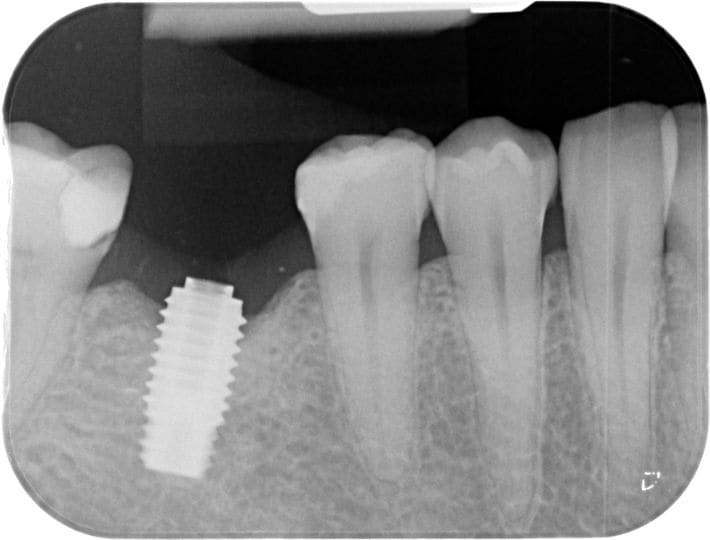

Je recherche une identification d'implant suite à fracture pilier.